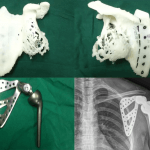

75% des Knochens wurden durch den Tumor zerstört, wodurch sich eine operative Entfernung des Tumors erschwerte, sollte es nicht auch zu einer Amputation von Arm und Schulter kommen. Dank der 3D-Technologie war es den Ärzten aber möglich ein exaktes Replikat des ursprünglichen Schulterblatts herzustellen. Mit Hilfe verschiedener Scans wurden Berechnungen durchgeführt, die den Zustand des Schulterblatts vor dem Angriff des Tumors rekonstruieren konnten. Mithilfe eines harz-basierenden 3D-Druckers konnte eine Schablone für das Schulterblatt gedruckt werden, welche wiederum an eine andere Einrichtung geschickt wurde, um aus dieser Vorlage ein Schulterblatt aus Titanium herzustellen.

Und tatsächlich konnte vor kurzem die Operation vorgenommen werden, in der ein neues Schulterblatt mithilfe des 3D-Druckers erfolgreich in den Körper eingesetzt wurde. Die Ärzte gehen davon aus, dass Li Jieyang vollständig gesundet und schon bald wieder Arm und Schulter normal bewegen kann.